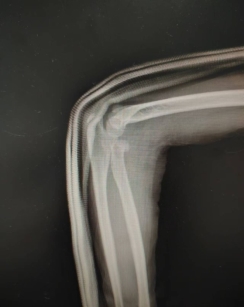

患儿,女,11岁,5月14日因“外伤后右肘肿痛1小时余”入院,术前X线提示右侧桡骨颈骨折,O’Brien分型Ⅱ型,入院后我科陈义权主任立即和张浩医生采用中医特色骨折夹板固定骨折处,于5月17日予右桡骨颈骨折闭合复位弹性髓内钉内固定术,术中我科陈义权主任采用Metaizeau技术,在腕部做一长约1cm切口,利用弹性髓内钉闭合复位骨折端。术后3月复查,骨折端基本愈合。我科成功将中医特色治疗与小儿骨折微创治疗技术完美结合。

图1:术前夹板固定后的X线片